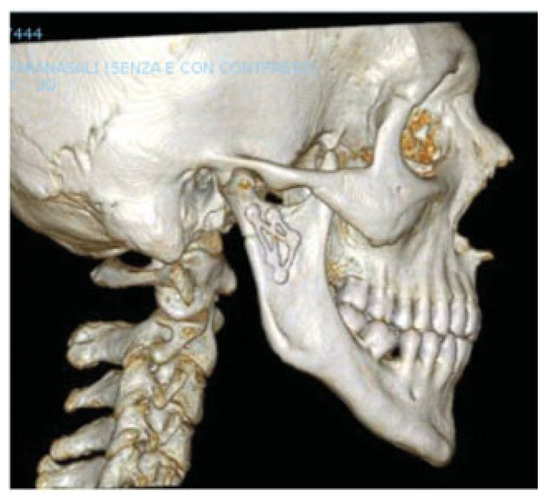

Development and Clinical Evaluation of MatrixMANDIBLE Subcondylar Plates System (Synthes)

Cortelazzi, R.; Altacera, M.; Turco, M.; Antonicelli, V.; De Benedittis, M. Development and Clinical Evaluation of MatrixMANDIBLE Subcondylar Plates System (Synthes). Craniomaxillofac. Trauma Reconstr. 2015, 8, 94-99. https://doi.org/10.1055/s-0034-1395382